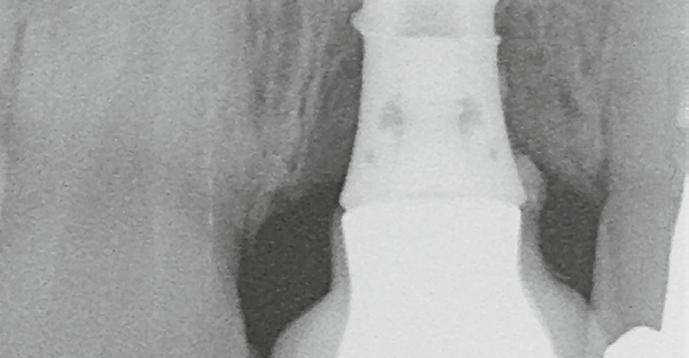

6. ábra: Klinikai helyzet a kezdeti vizsgálat során. 9 mm mély periimplantáris szondázási mélység, szondázási vérzéssel. Az arc periimplantáris nyálkahártyáján sinus felőli szivárgás figyelhető meg. A periimplantitis diagnózisának felállítása előtt körülbelül 4 évvel, amikor a pácienst kezelésre utalták, cementált fogpótlást helyeztek el ezen a Straumann lágyrész-szintű implantátumon.

7. ábra: Röntgenfelvétel a marginális csontszintekről az implantátumnál a kezelés előtt. Meziális és disztális csontvesztés figyelhető meg, amely az implantátum második menetéig terjed. Figyelje meg az implantátum disztális felszínén lévő radioopak anyagot (felesleges rögzítőcement)! Figyelje meg a 11-es fog meziális felszínén lévő fogkövet is!

8. ábra: A csonton belüli defektus palatinális nézete. Vegyük észre, hogy a szájpadlás felőli csontfal ép, így ez a defektus alkalmas a regenerációra!

9. ábra: Felvétel az implantátumról és a csontdefektusról a lebenyképzés után, az implantátum és a korona felszínén lévő felesleges rögzítőcement eltávolítása előtt.

10. ábra: A gyulladásos granulációs szövet eltávolítása és az implantátum felületének dekontaminálása után a defektus csonton belüli részét Geistlich Bio-Oss® granulátummal töltjük fel. Megjegyzendő, hogy a korona kontúrja és marginális illeszkedése nem ideális, azonban a páciens nem kívánta a korona eltávolítását.

11. ábra: Az augmentált területet a Geistlich Bio-Gide® natív kollagénmembránnal fedjük be.

12. ábra: Posztoperatív nézet a varratszedés után. A mukoperioszteális lebeny lezárása a membrán fedésére és a varratok elhelyezése. 13. ábra: Klinikai helyzet 4 hónappal az implantátum regeneratív sebészeti kezelése után. 14. ábra: A 12 hónappal a műtét után készült ellenőrző röntgenfelvétel stabil csontszintet mutat, a defektus teljesen feltöltődött.